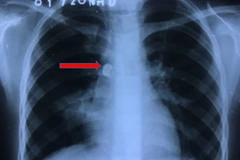

Bệnh nhân tử vong ngày 15/5/2021 với chẩn đoán suy hô hấp, viêm phổi nặng do SARS-CoV-2, tăng huyết áp, đái tháo đường, tiền sử xẹp đốt sống thắt lưng đã phẫu thuật.